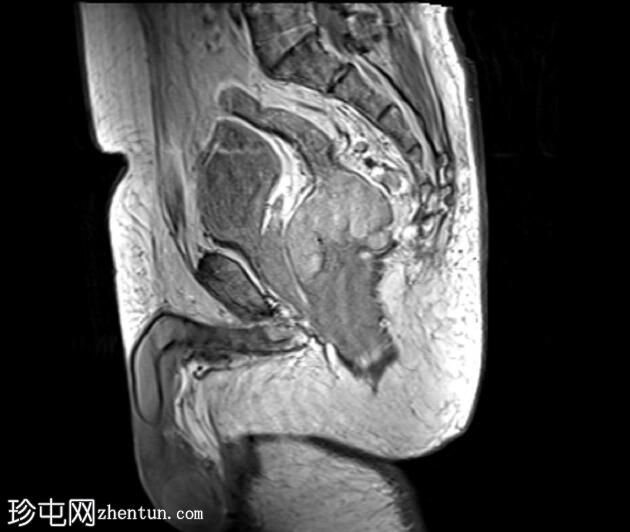

矢状位

PD加权像

5.jpeg

可见一不规则分叶状肿块,累及直肠中段和远端,头尾方向长约7 cm,下缘距肛缘约2.5 cm。在T1加权像和T2加权像上,该病灶相对于骨骼肌均呈高信号。 PDFS(脂肪抑制)图像显示持续高信号强度,提示存在黑色素和/或出血成分。

增强扫描显示病灶内呈不均匀强化。直肠下段7点钟位置的系膜筋膜受累。后方系膜可见少量淋巴结。未见邻近器官侵犯。